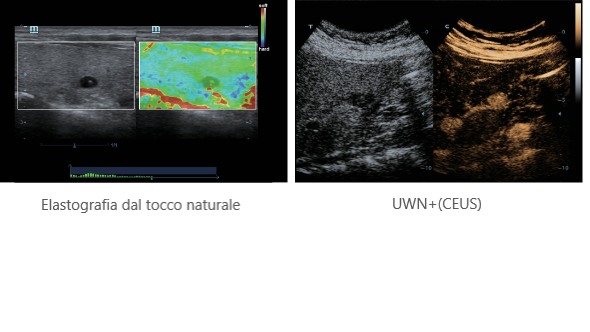

Elastografia dal tocco naturale

UWN+(CEUS)